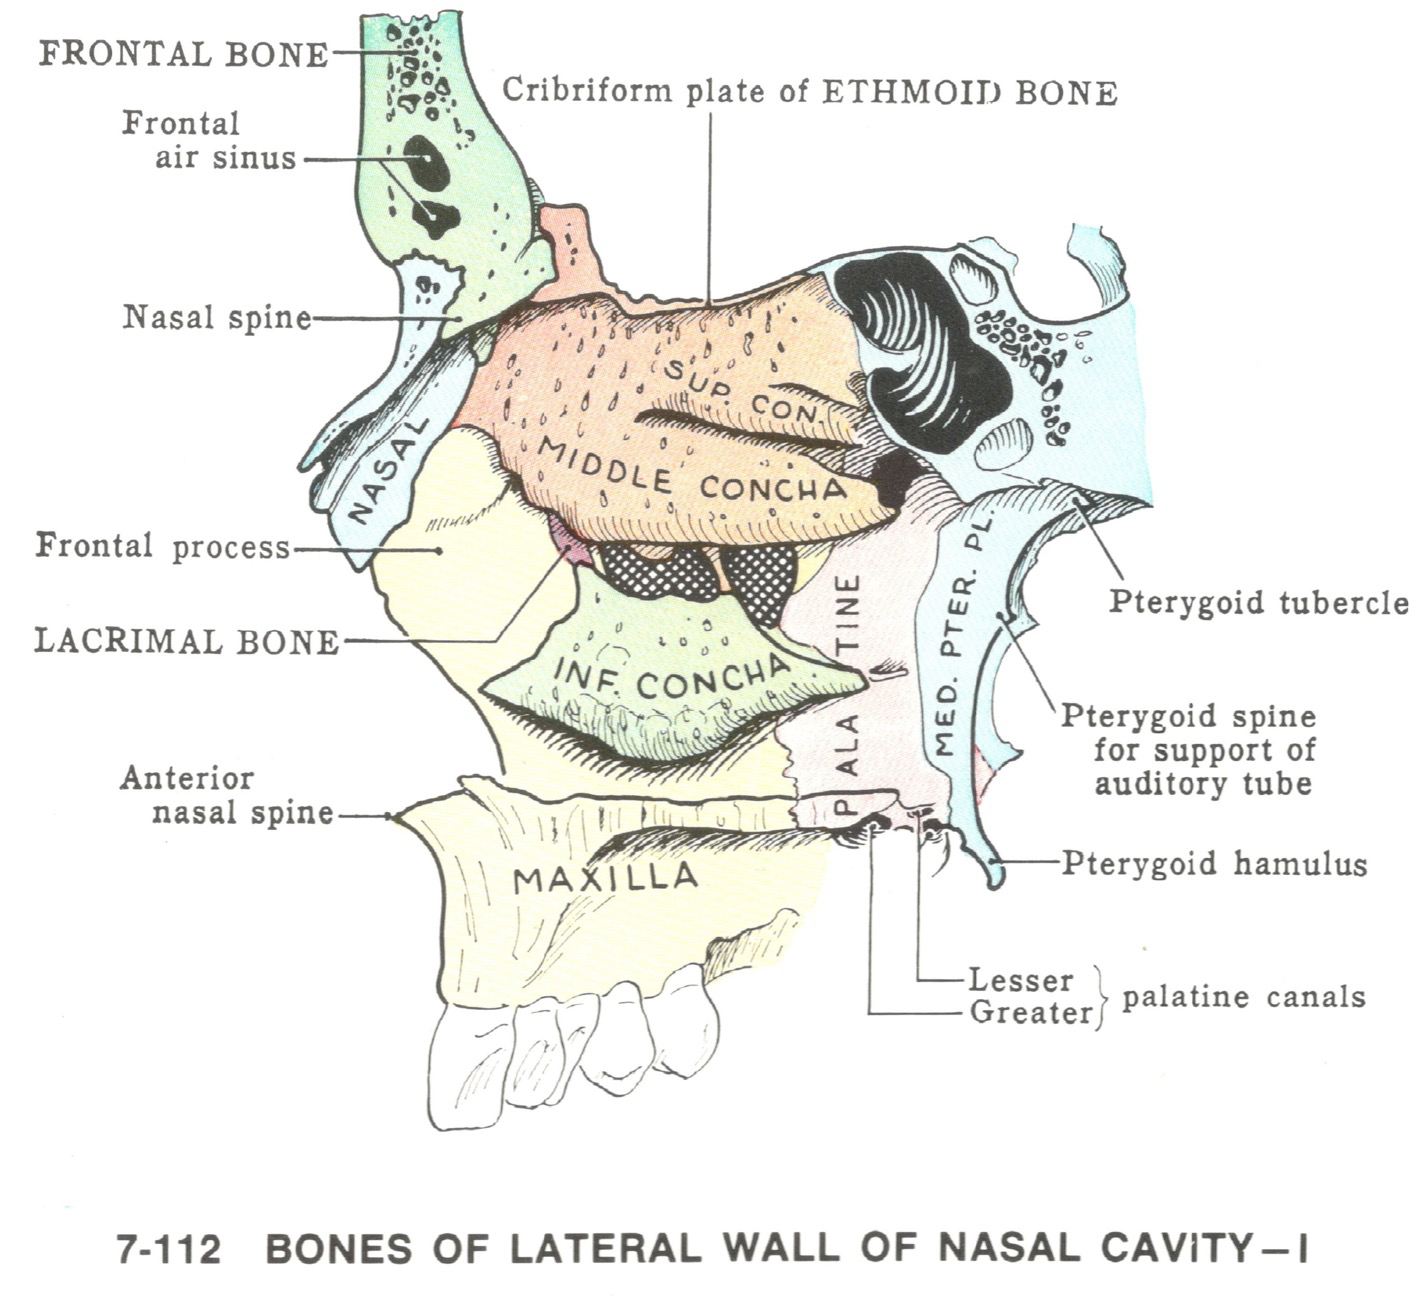

Ethmoid bone

- superior and middle Nasal concha

inferior Nasal concha

Temporal bone

Maxillary bone

Palatine bone

Lacrimal bone

Bone

- Frontal (nasal process)

- Maxilla (frontal process)

- Nasal

Nasal septum (鼻中膈)

- nasal sepal cartilage

- perpendicular plate of ethmoid

- vomer